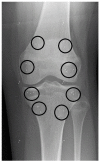

Methods: Radiostereometric analysis, with implantation of tantalum balls as radiographic markers on each side of the physes, was used to measure residual longitudinal growth in 21 children (10 boys and 11 girls) after percutaneous physiodesis for leg length discrepancy or extreme tall stature. In total, 25 femoral and 20 tibial physes were operated on. Median age at surgery was 13.9 years (range = 11.4-16.1). Radiostereometric analysis was performed postoperatively and after 3, 6, 9, 12, 26, and 52 weeks. Longitudinal growth rate <50 µm per week was defined as physeal arrest. Descriptive statistics were used for evaluation.

Figures